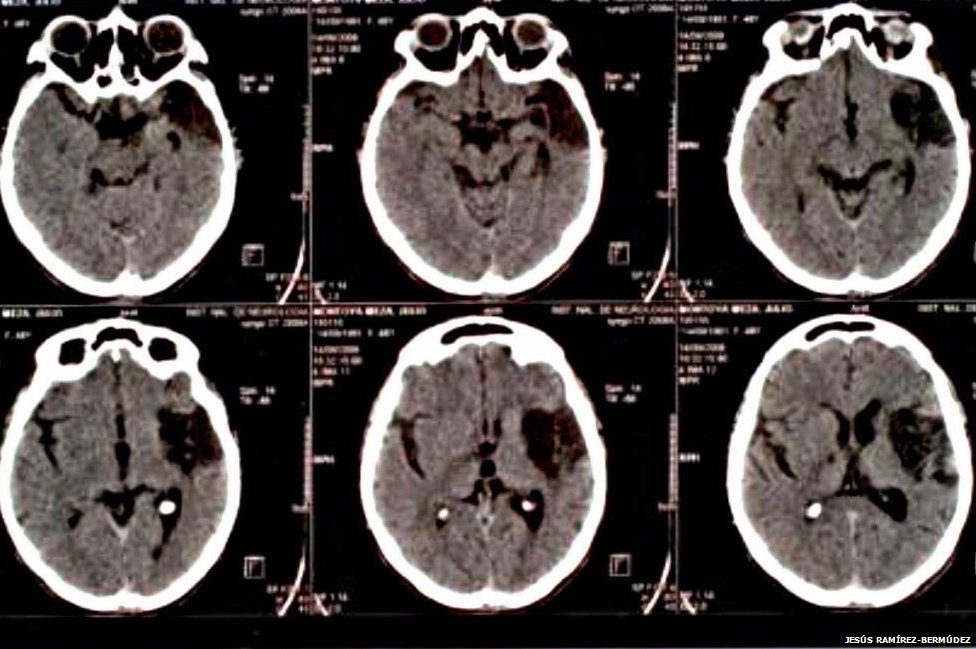

Un estudio realizado en 2010 por el Instituto Nacional de Neurología y Neurocirugía de México halló que el síndrome suele ser el resultado de dos factores que se combinan.

Los indicios neurológicos incluyen un índice metabólico muy bajo en regiones del cerebro responsables de la introspección, el achicamiento o aumento del cerebro y el daño a la parte del cerebro que está detrás de la frente, que controla los pensamientos, el razonamiento y el comportamiento.